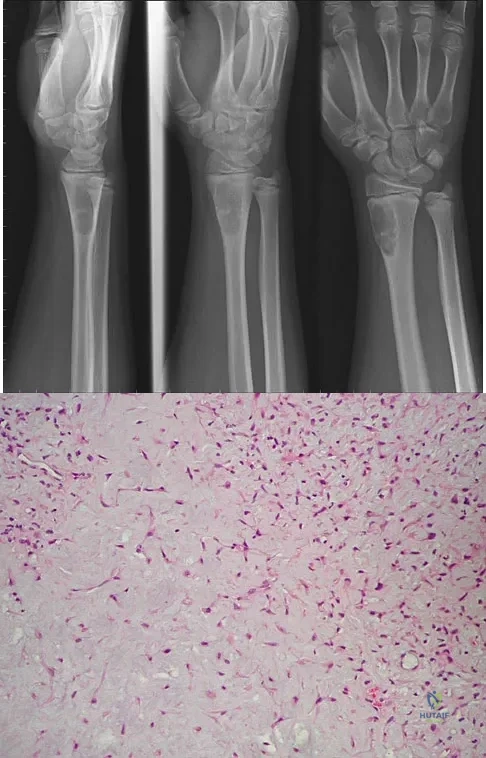

A 16-year-old boy has had left knee pain and swelling after sustaining a minor twisting injury while playing basketball 2 weeks ago. Figures 5a through 5e show the radiograph, MRI scans, and biopsy specimens. What is the most likely diagnosis?